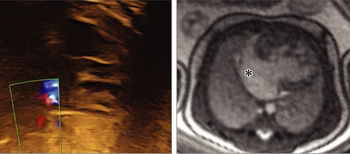

A 43-year-old male presents for suspected PE evaluation. What is the diagnosis?